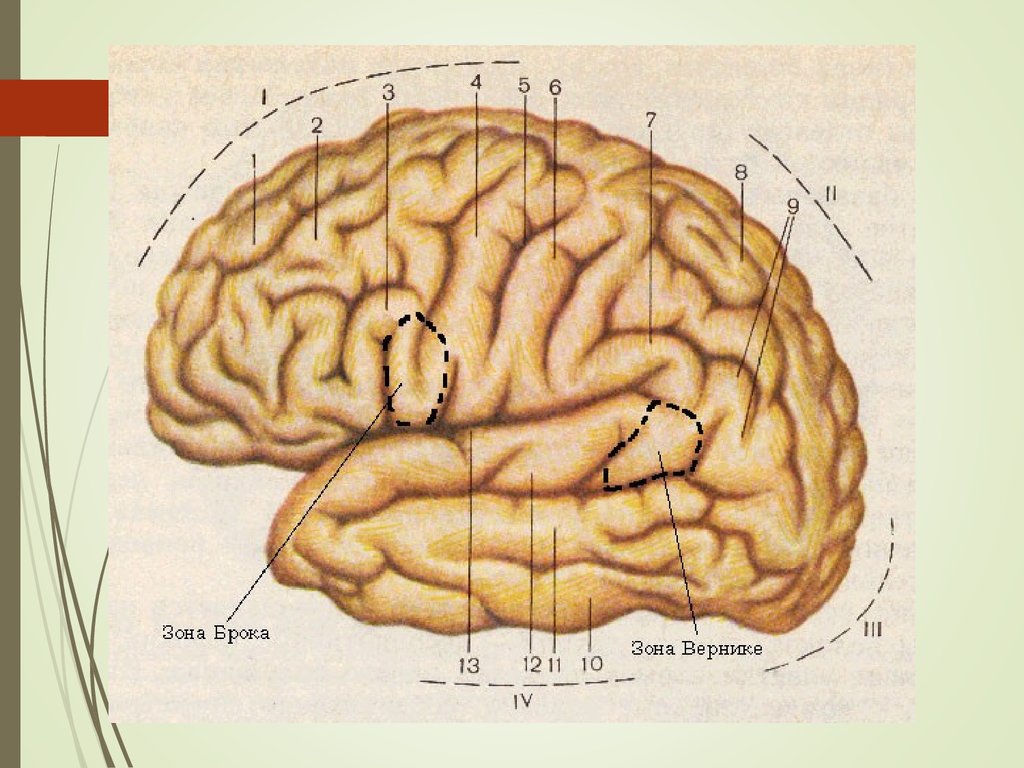

Анатомические снимки верхнелатеральной поверхности головного мозга